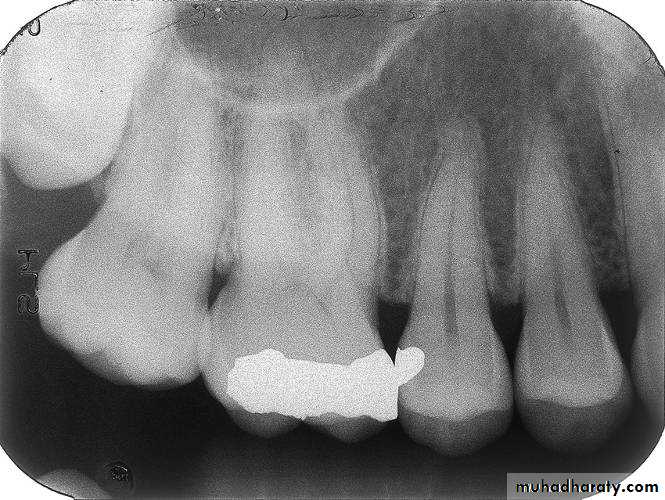

Bite-wing Radiography

• Indications:• Interproximal caries.

• Over-hang filling.

• Level of crestal bone between the teeth.

• Interproximal calculus.

• Principles:

• The film is placed in the mouth parallel to the crown of both upper & lower teeth.

• The film stabilized when the patient bites on the bite-wing tab or bite-wing film holder.

• The central ray of the x-ray beam is directed through the contacts of the teeth, using a +10 degree vertical angulation.

+10o vertical angulation is used to compensate for the slight bend of the upper portion of the film and the tilt of the maxillary teeth.

The molar-bitewing. A, Film placement. B, Resultant radiograph.

A

B